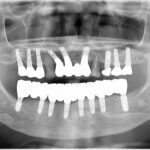

山内歯科のインプラントが何故、選ばれるか。 インプラント治療は失ってしまった歯を取り戻す、唯一の素晴らしい治療法です。 ...

上あごの骨が少なくインプラントが難しい場合 「骨が少ないので、インプラントは難しいかもしれませんね・・・」 そんな場合で...